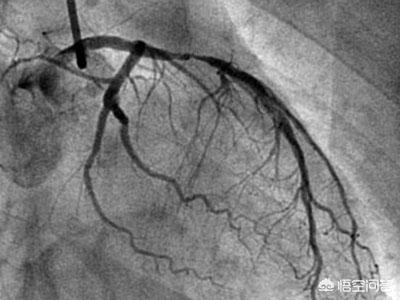

1.冠動脈造影は確かに冠動脈疾患の診断のゴールドスタンダードであり、冠動脈の様々な枝の狭窄病変の位置を明確に同定し、その範囲と血管全体の血液供給を推定できる動的検査である。しかし、この検査は大腿動脈または橈骨動脈を経由して行わなければならない侵襲的な検査であり、検査費用が相対的に高くつくので、この検査を受けるのに適さない患者もいる。

まず、冠動脈造影は単なる検査であり、冠動脈疾患の重症度を評価し、冠動脈疾患の治療効果を評価し、冠動脈疾患の有無を確認するための重要な検査であることを明確にしなければなりません。そのため、冠動脈疾患と診断された多くの患者さんにとって、冠動脈疾患の治療効果を明らかにするため、また冠動脈疾患の重症度を評価するために、冠動脈造影検査を選択し、状態を評価し、治療を指導しなければならないことがよくあります。

冠動脈造影とは何ですか?

冠動脈造影検査は、他のルーチン検査と違って、同様の検査に比べて患者に害を及ぼす可能性があるため、クリニックで気軽に行うことはできず、できることなら行わないのが原則である。

冠動脈造影検査は冠動脈疾患の診断を確定するためのゴールドスタンダードの一つであり、冠動脈狭窄の程度を明らかにする上で非常に重要な役割を果たしている。冠動脈のアテローム性動脈硬化症による冠動脈性心疾患患者にとって、現在の医療状況では、有効な治療法はなく、長期的な治療が必要であり、病状を安定させ、コントロールし、合併症の発生を減らすためには、定期的な治療と同時に、病状の変化のモニタリングと定期的な見直しに注意を払う必要があり、病状のコントロールの定期的な見直しと個別化されたプログラムの開発を遵守することは、かけがえのない役割を担っています。冠状動脈性心臓病の患者は定期的に見直すべきである。

冠動脈性心疾患とは、冠動脈の動脈硬化が原因で起こる心臓病で、冠動脈の狭窄や閉塞により虚血、低酸素、心筋細胞の壊死が起こる。冠動脈疾患の診断には、臨床症状、臨床検査、心電図、冠動脈CT、冠動脈造影などの総合的な判断が必要である。